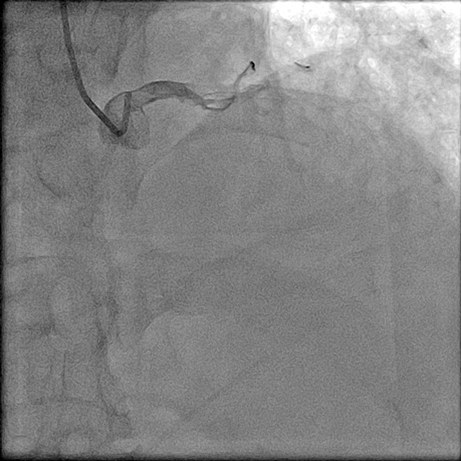

【临床病例】心肌梗死、心力衰竭患者心室率控制不佳怎么办?--新型If通道阻滞剂的应用

文章来自:中山二院心脏病MDT 叶伟斌 张坤